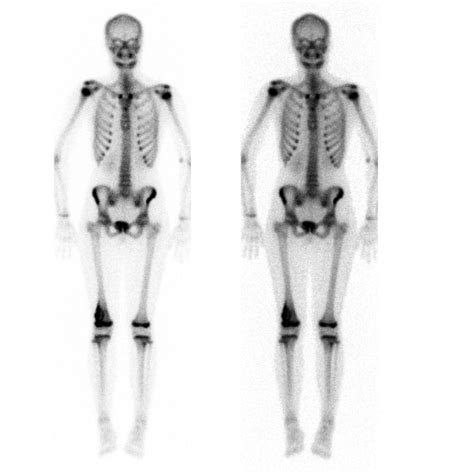

Furthermore, because an X-ray only shows the bone and some soft tissue shadows, it cannot accurately show the full extent of the disease. After the initial X-ray raises suspicion, further imaging is required:

• CT Scan (Computed Tomography): Often used to scan the lungs to check for potential metastatic spread.

• Bone Scan/PET Scan: Used to evaluate the entire skeleton for other potential sites of spread (metastasis).

As treatment protocols continue to evolve, the initial identification of these tumors remains the cornerstone of successful outcomes. Modern surgical techniques, combined with advanced chemotherapy regimens, have significantly improved survival rates over the past few decades. These advancements are only effective if the tumor is identified and staged accurately, beginning with that initial, vital radiographic investigation.